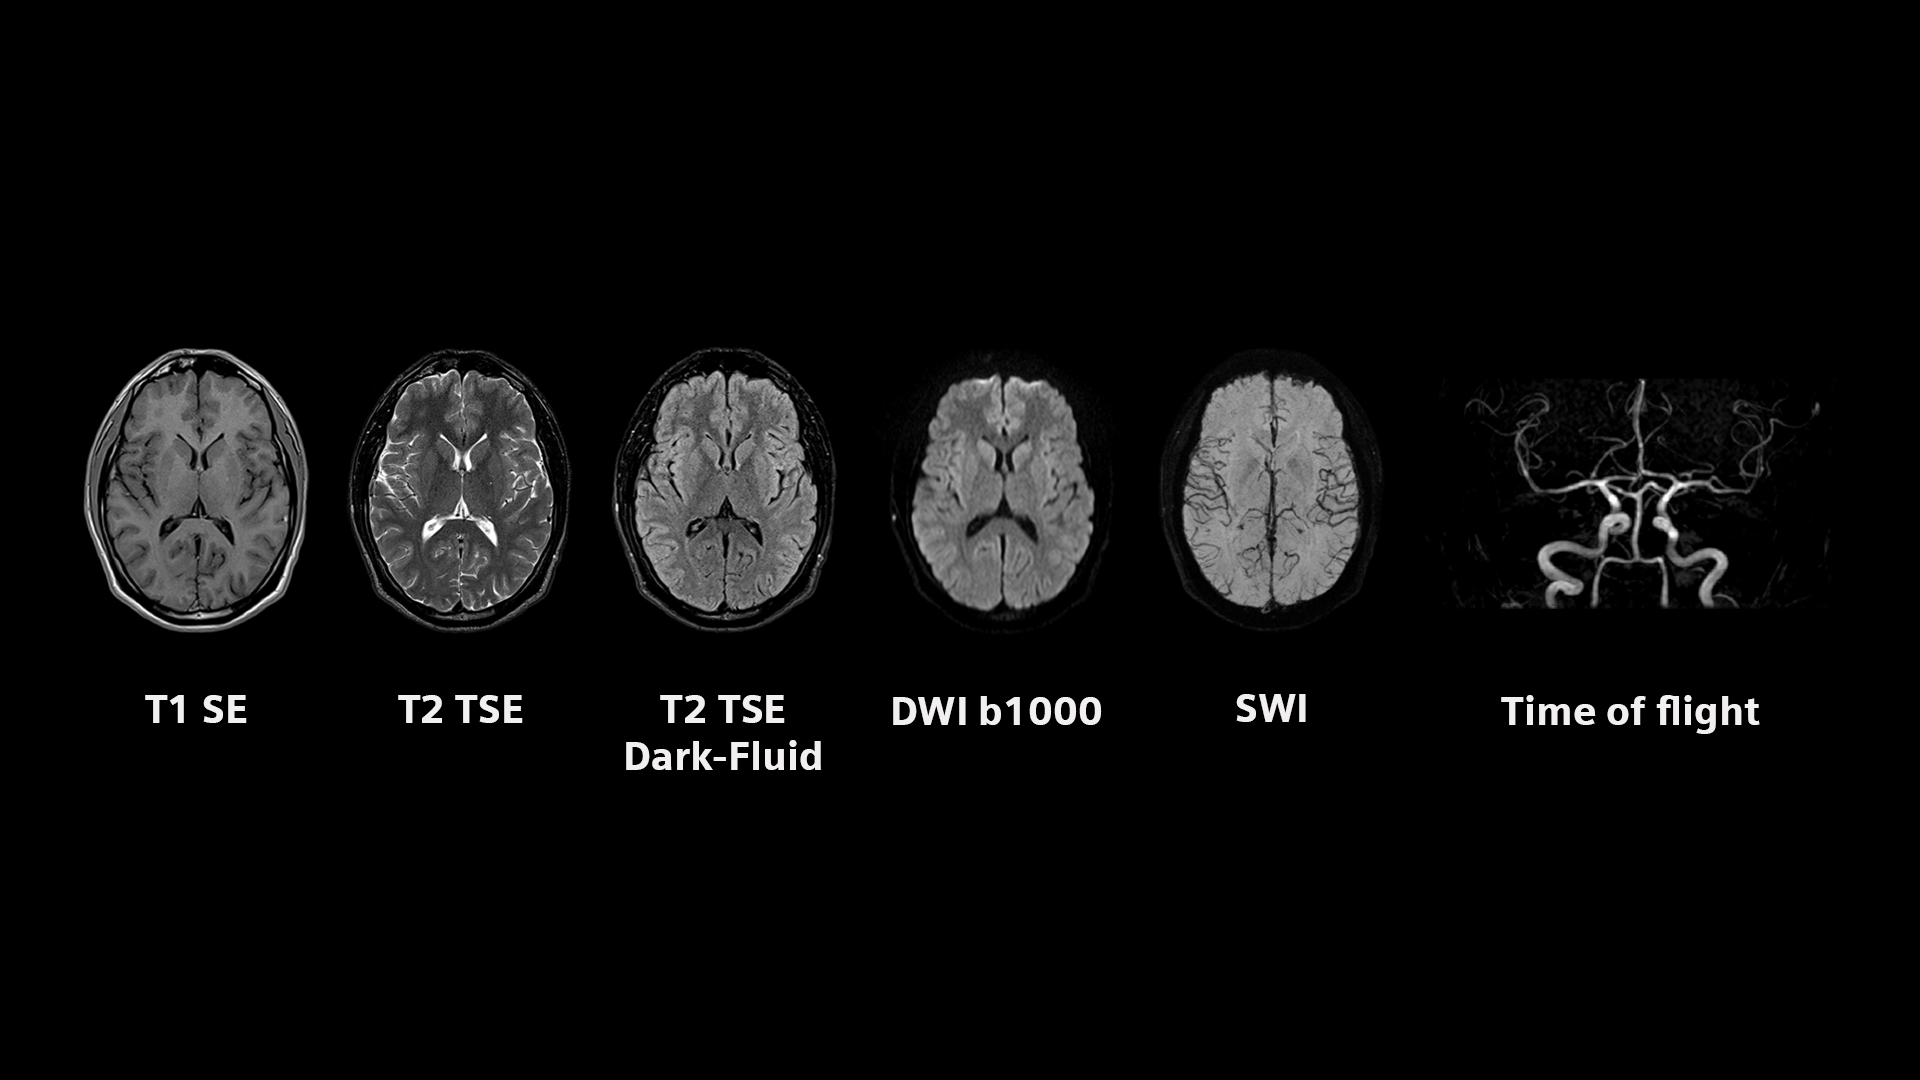

Press Pictures

www.siemens-healthineers.commax siemens press healthineers mri

www.siemens-healthineers.commax siemens press healthineers mri

theposterdb.comMedical Arts Radiology | MRI Commercial

theposterdb.comMedical Arts Radiology | MRI Commercial

www.pinterest.comradiology mri radiologic technologist radiologist imaging geometric blue radiologists direct

www.pinterest.comradiology mri radiologic technologist radiologist imaging geometric blue radiologists direct